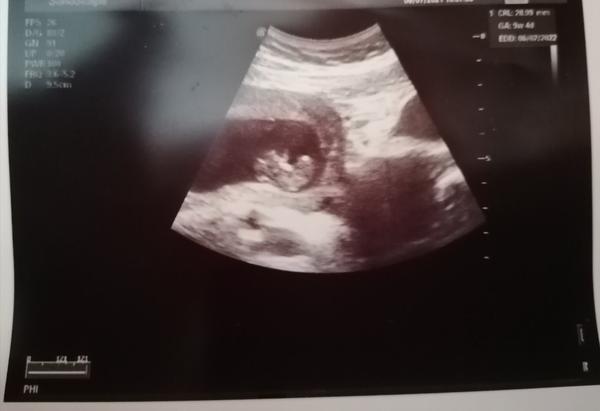

poslední MS byla 28.4 a pozitivní ovu test 14.5 (17DC) Měla bych být dnes 10+0tt, 24.6. jsem byla dle utzv 8+0tt.... Dneska po utzv pan doktor říkal, že je vše v pořádku srdíčko bije, ale na fotce mám 9+4tt což o 3dny nevychází, ale říkám si, že je tam určitě nějaká odchylka a navíc mi dělal utzv přes břicho, takže to tak přehledné nebylo. CRL 28.99mm, myslíte že ty 3 dny jsou ok? Děkuji za odpovědi.